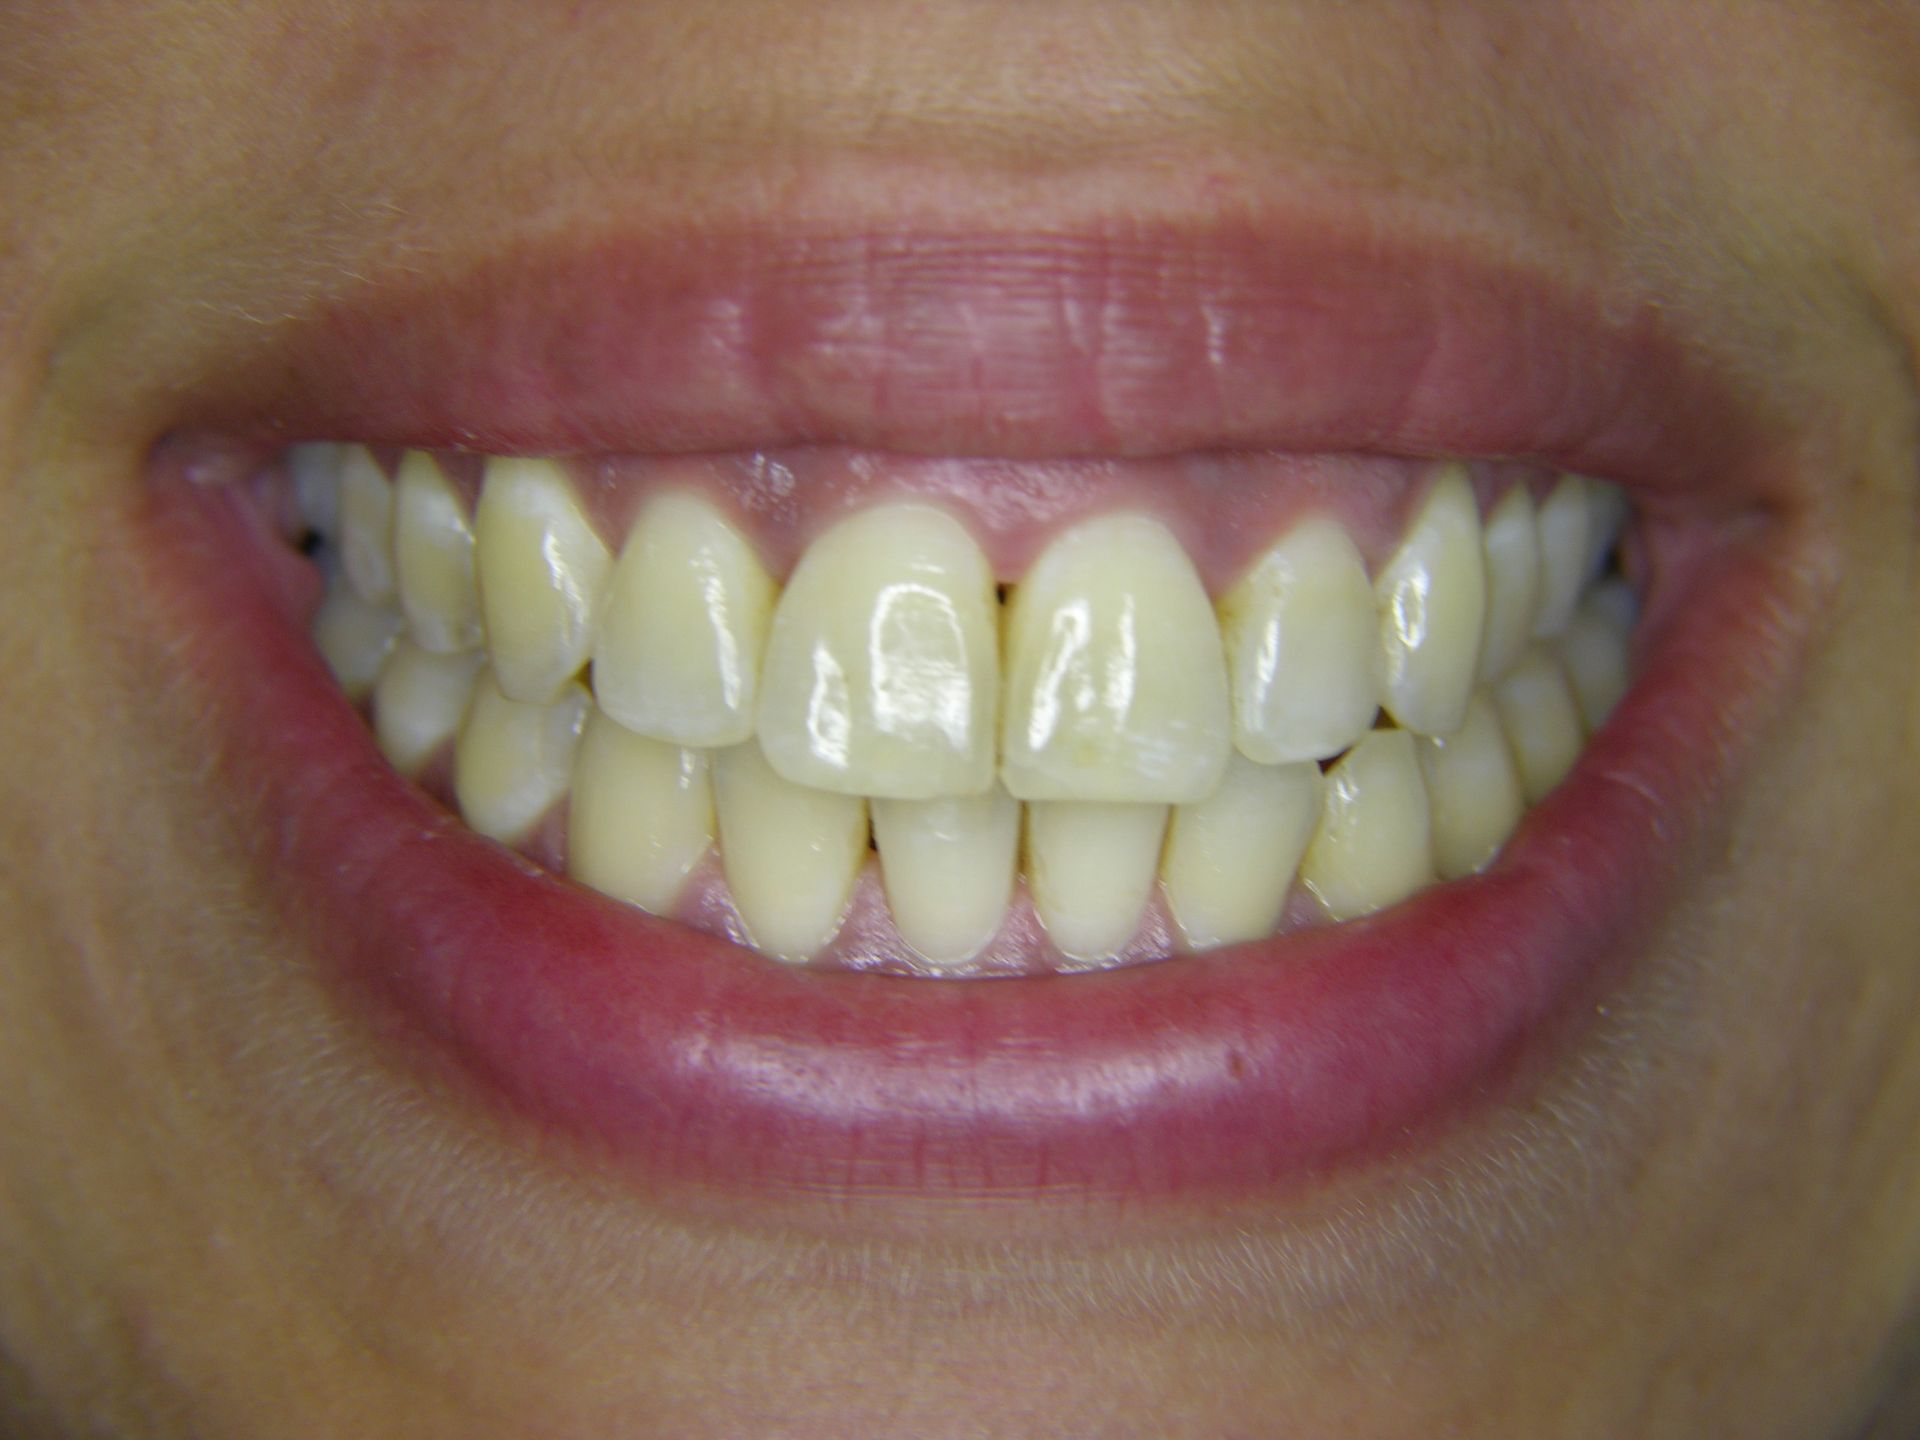

Beispiele von Versorgungen